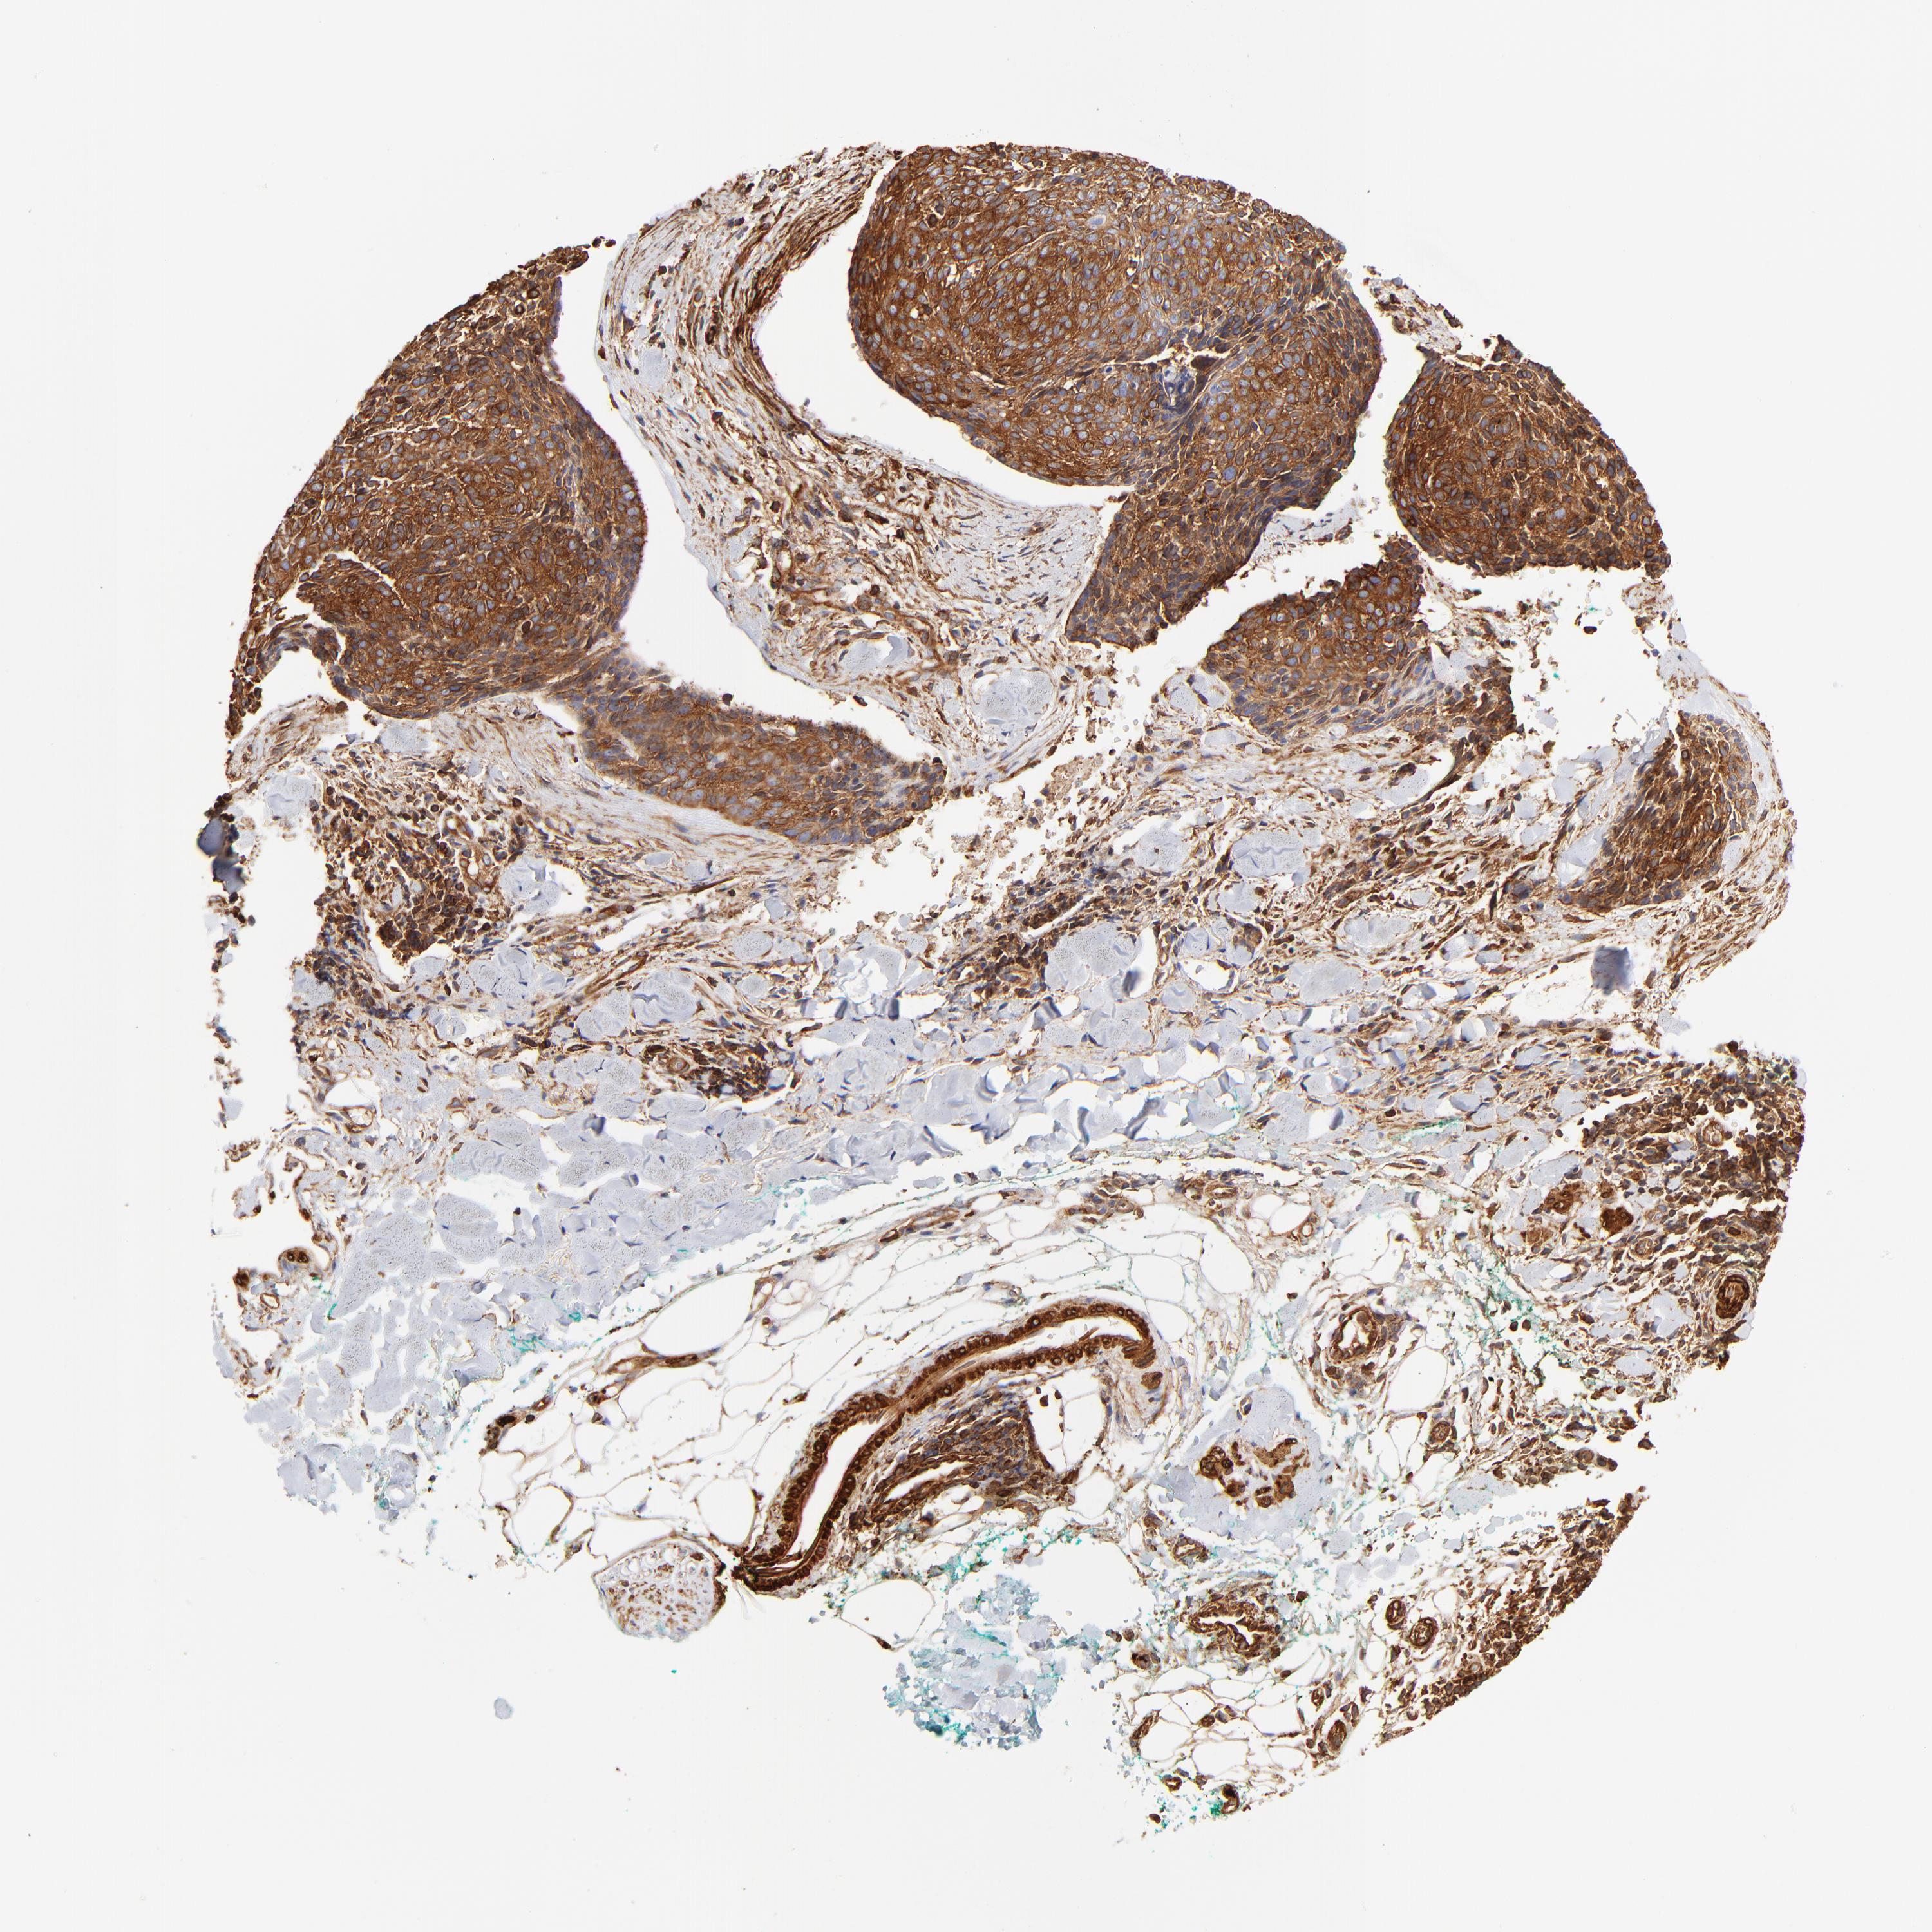

SKIN CANCER - Protein expressioni

A mouse-over function shows sample information and annotation data. Click on an image to view it in a full screen mode. Samples can be filtered based on level of antibody staining by selecting one or several of the following categories: high, medium, low and not detected. The assay and annotation is described here.

Antibody stainingi

Antibody staining in the annotated cell types in the current human tissue is reported as not detected, low, medium, or high, based on conventional immunohistochemistry profiling in selected tissues. This score is based on the combination of the staining intensity and fraction of stained cells.

Each image is clickable and will lead to virtual microscopy that enables deeper exploration of all samples and also displays staining intensity scores, fraction scores and subcellular localization as well as patient and tissue information for each sample.

Antibody HPA001115

Antibody HPA002925

Antibody CAB000356

Staining

High

Medium

Low

Not detected

Intensity

Strong

Moderate

Weak

Negative

Quantity

>75%

75%-25%

<25%

None

Location

Nuclear

Cytoplasmic/membranous

Cytoplasmic/membranous,nuclear

Squamous cell carcinoma, NOS

Basal cell carcinoma